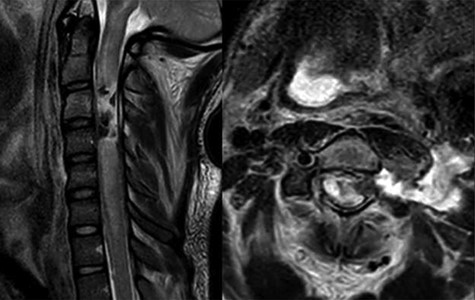

Cervical gunshot wound cerebrospinal fluid fistula treatment algorithm.

In the setting of a cervical gunshot wound with csf fistula, the authors propose a new treatment algorithm (Fig. 4) flowchart developed based on our clinic experience and a thoughtful review of the literature. Patients initially deemed nonoperative patients should be observed for spontaneous resolution. Patients should be evaluated for a myelographic block with either a CT myelogram or MRI if the leak persist. A lumbar drain can be placed if there is no myelographic block. In patients where a lumbar drain is ineffective secondary to a myelographic block or severe canal narrowing, an EVD should be considered followed by surgical exploration and repair. In operative patients, a primary closure or patch repair should be attempted with fibrin glue. An adjuvant lumbar drain should be considered. In the setting of severe arachnoiditis, adhesion formation or myelographic block an EVD should be used if csf leak persist despite surgical repair. Although, the authors do not have direct experience with csf fistula related to thoracic gunshot wounds, a similar algorithm seems reasonable. The current treatment algorithm was developed through our clinical experience and thoughtful review of the literature. The authors recognize that our findings are limited by the small size of our case series, and that a larger series or prospective trail may provide more information.